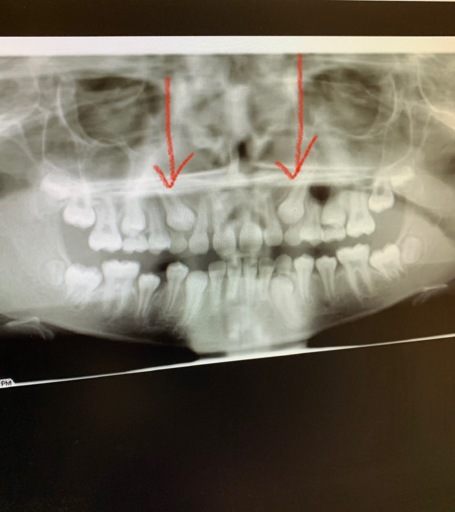

Number 30 molar

This tooth has had a root canal and a crown installed several yrs, ago. Now my dentist says the ex ray shows that the root has now separated and one side broke, therefore the tooth should be removed. Is that correct? I would then have to get a bridge or implant, or just have an empty space. I have all my other teeth except the 4 wisdom teeth. I don't like this situation. Any other possibility?